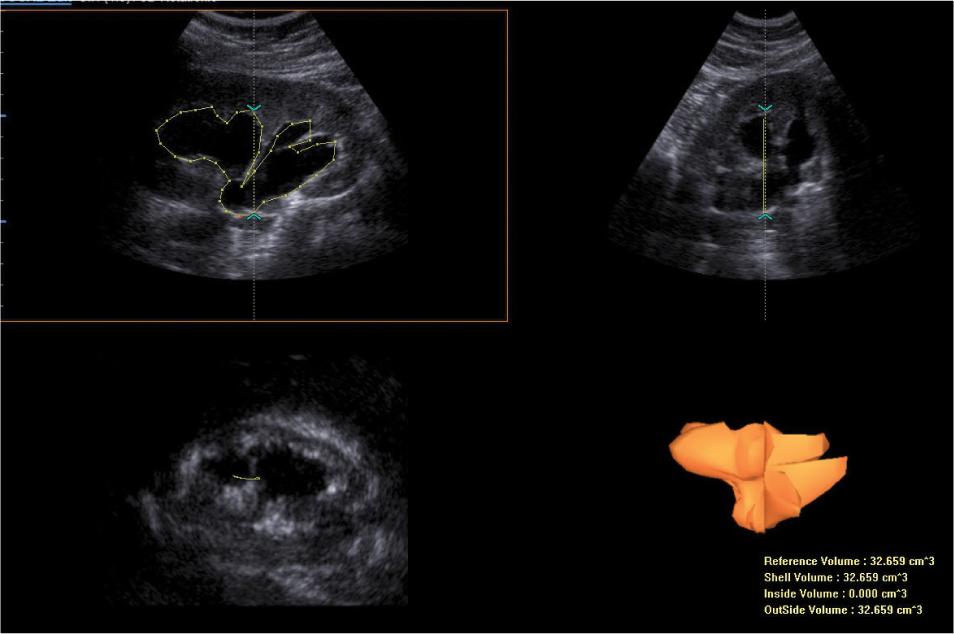

Fig. 6.

Three-dimensional ultrasound assessment of urine retention volume in the pelvicalyceal system. The VOCAL software has been used for volume calculations. Estimated pelvicalyceal volume = 32.66 cm3. The case presented in Fig. 3